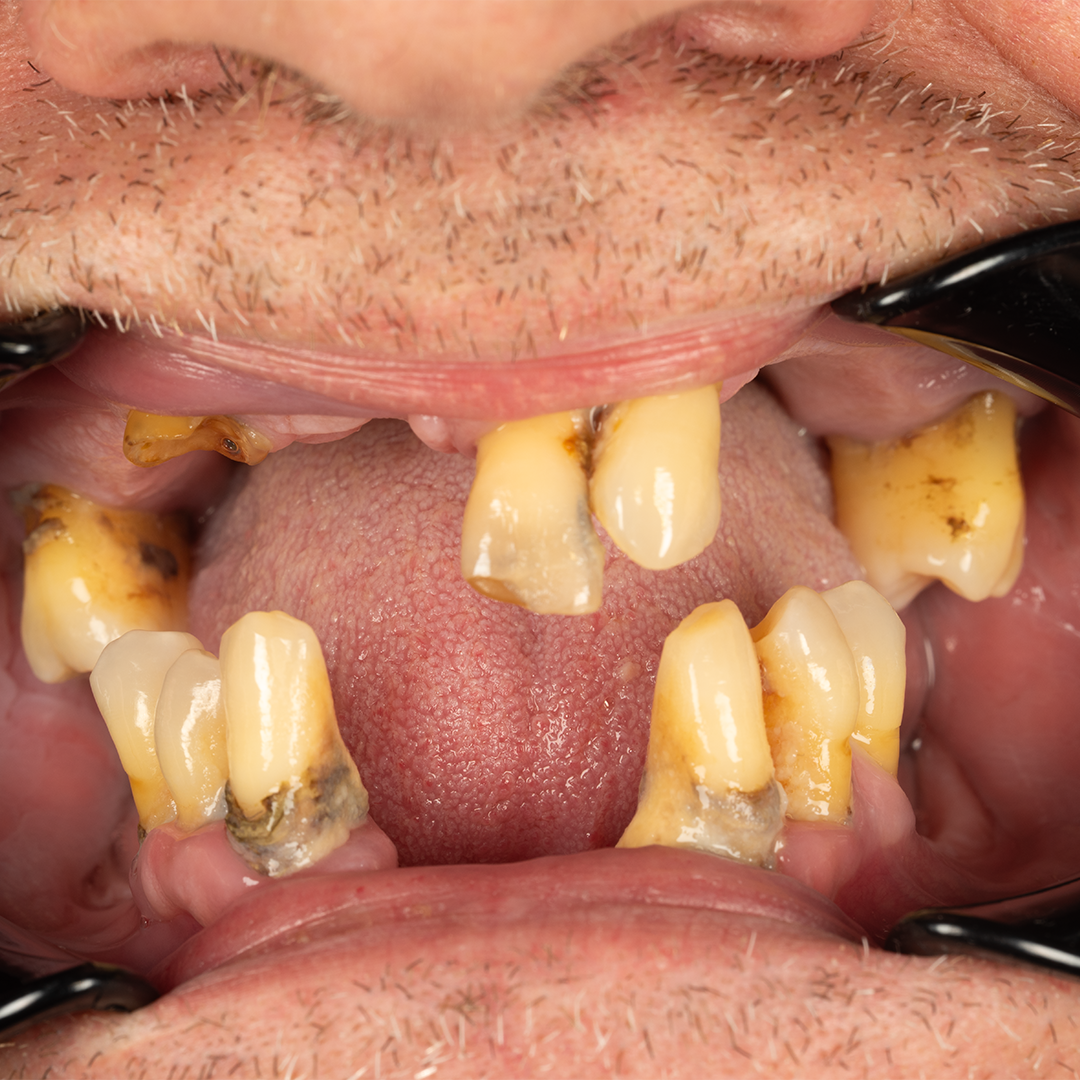

Cazuri Clinice Reale

Rezultate obținute în clinica noastră. Imaginile sunt prezentate cu acordul pacienților.

Caz 2 - Înainte Zona Laterală Înainte

Caz 2 - După După

Pacient I.S. (45 ani)

Stabilitate la masticație și confort zilnic.